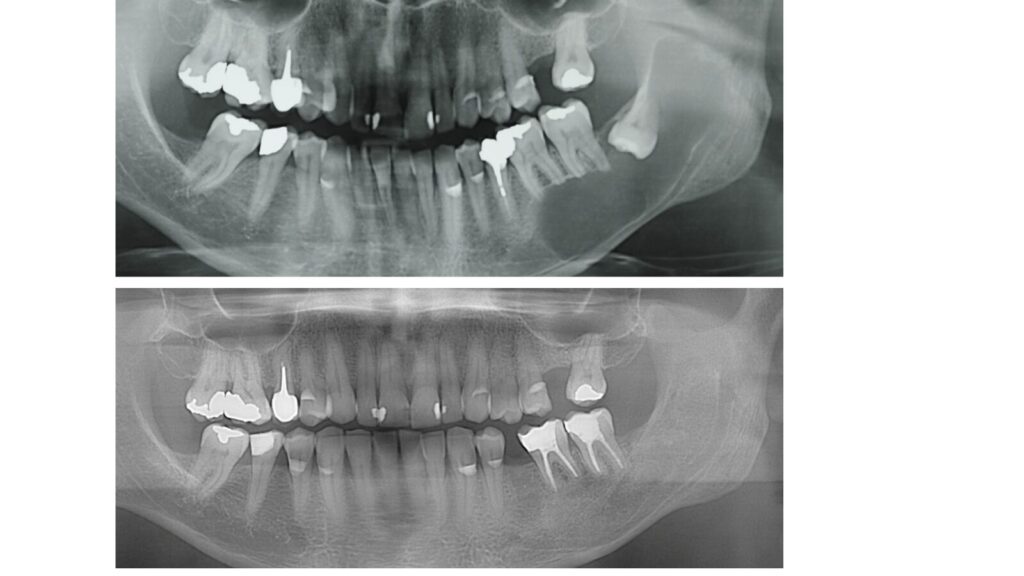

- INDAGINE DIAGNOSTICHE (radiografie indorali,OPT,TC)

- INTERPRETAZIONE PRECHIRURGICA DELLA TC

Dentascan e CBCT (Tac Cone Beam) - TECNICHE ANESTESIOLOGICHE

- VALUTAZIONE DI CASI CLINICI

• VALUTAZIONE DI CASI CLINICI

• VALUTAZIONE DEL RISCHIO NEUROLOGICO

• III° MOLARI ASSOCIATI A CISTI